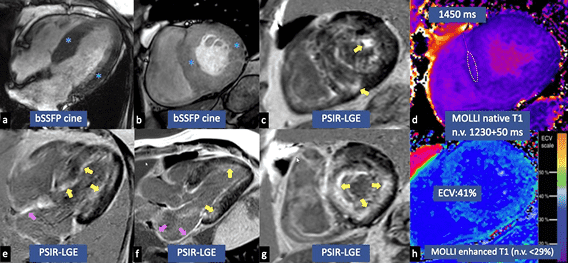

ECHO4

- Hypertrophic phenotype with infiltrative features

- Restrictive LV filling with RV wall thickening

- Reduction in global longitudinal strain